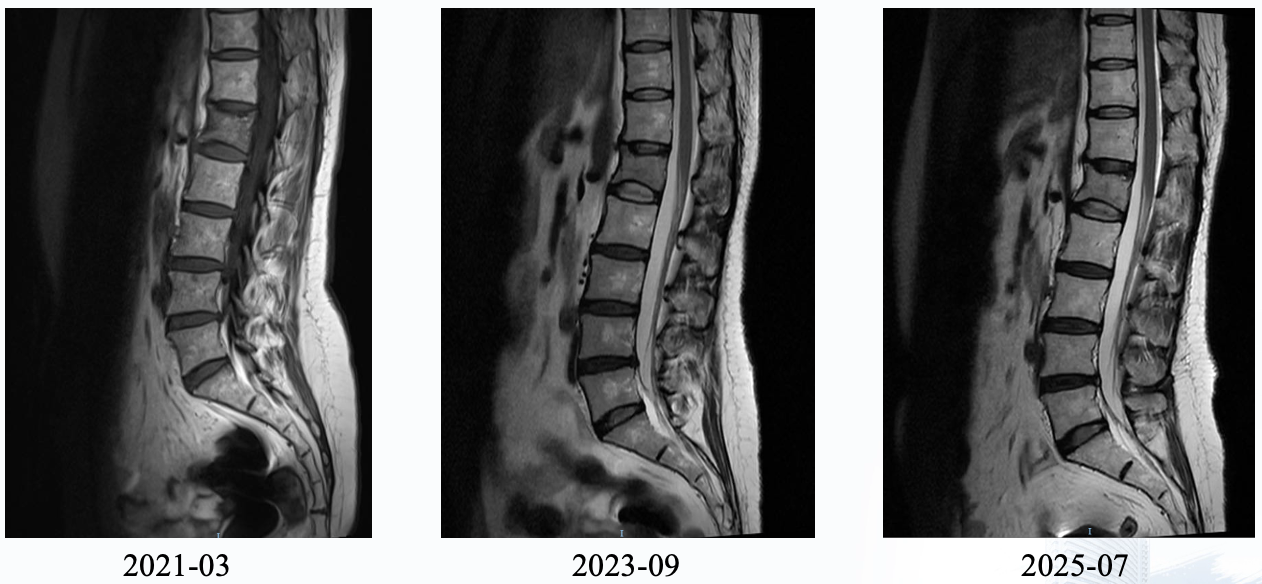

理论的终点是实践。江苏省人民医院华一佳医生分享的一例跨度长达9年的绝经前晚期乳腺癌病例,生动诠释了慢病化管理的精髓。

该患者为49岁Luminal B型乳腺癌女性,2012年术后,2016年出现多发骨、肝转移。在经历一线吉西他滨及紫杉醇化疗不耐受或仅获稳后,患者自2017年起接受了CDK4/6抑制剂(哌柏西利)联合内分泌治疗的维持方案。这一组合展现了持久疗效,虽然中途因注射硬结将氟维司群调整为口服依西美坦,但截至汇报时,患者PFS已超过9年,病灶持续稳定,且保持了极高的生活质量。

针对患者存在的骨转移和肝转移病灶,是否需要引入局部治疗(如放疗、消融等),Hope Rugo教授持审慎态度。她认为,目前的证据并不支持在广泛转移的情况下通过局部治疗改变最终结局,反而可能增加治疗毒性或并发症。她强调,除非是为了缓解症状(如骨痛),否则应以系统治疗为主。王涛教授表示认同,指出晚期乳腺癌的治疗应是全身与局部的有机结合,但在该病例中,全身控制良好,局部治疗并非当务之急。